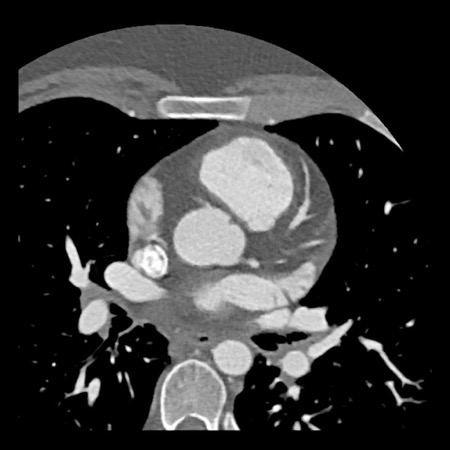

case 1 – CAD-RADS 2/P1

First, scroll through the scan.

Not all images are included. Some images without any abnormalities are skipped

from the series.

How would you describe the findings on the coronary CTA?

The findings are:

- Agatston score of

this patient was 14 (P1). Please, also note the calcification of the aortic valve. - Some partially

calcified and calcified plaques are present in the LAD with mild stenosis

(25-49%). - Calcified-plaque in

the LCX causing minimal stenosis (<25%). - Non-calcified

plaque in the distal RCA causing minimal stenosis (<25%). - This patient classifies

as CAD-RADS 2/P1, which means no further workup is needed.